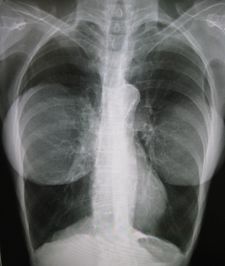

زراعة الثدي: تظهر صورة الصدر السينية لامرأة مزروعة ثديين أن الأطراف الاصطناعية غير شفافة من الناحية الإشعاعية ، وهي أشياء غريبة في جسمها ، ولكنها ليست من جسدها.